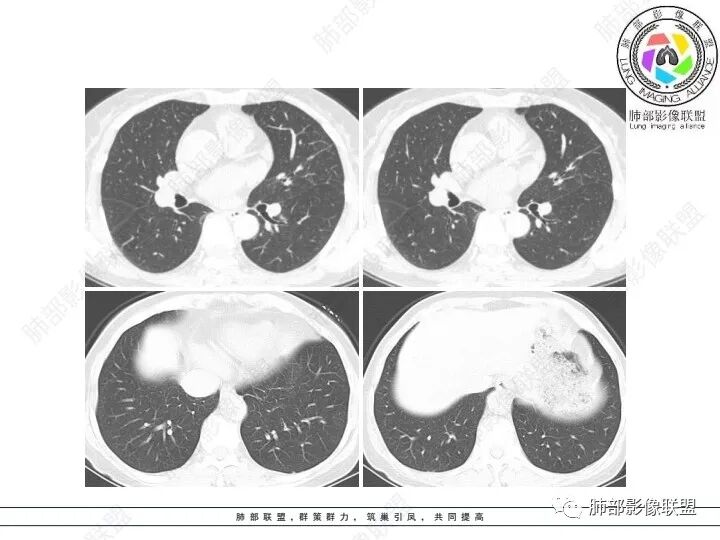

1、临床特点:61岁女性,体检发现肺结节。

2、影像特点:左肺上叶不规则病灶,冠状位、矢状位、斜状位重建显示病 灶整体沿着支气管方向呈斑片状,多结节堆积感明显,病灶大部分边缘显示平直,局部边缘稍膨隆,边界显示比较清楚,近端支气管壁显示增厚,周围可见长索条影及多发结节影,未显示典型“树芽征”。邻近叶间裂未受牵拉凹陷。纵隔窗显示病灶中央可见点状高密度钙化影。

3、病例小结:老年女性体检发现肺部结节,缺乏临床表现,需要警惕恶性。结合影像特点,左肺上叶病灶整体缺乏膨隆感,边缘大多平直,周围多发卫星灶(可见多发长索条影、并非肺CA的细短毛刺),病灶收缩力很弱(邻近叶间裂未见明显凹陷),观察1mm重建图亦可以发现病灶周围没有边界清楚的GGO,病灶内可见钙化点,肺门纵隔未见肿大淋巴结。综合以上,此病灶首先考虑炎性,结核可能性大,有条件可以增强扫描,有助于我们进一步判断。